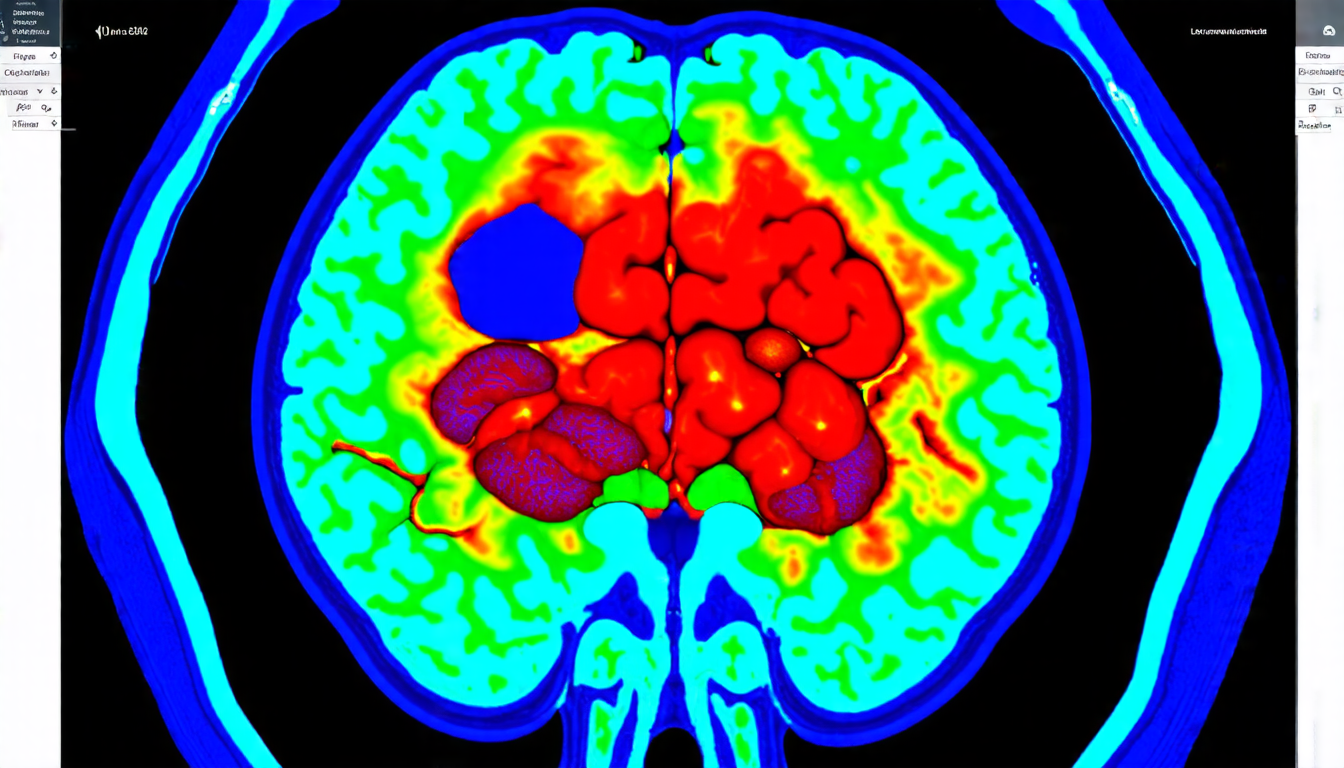

A team of researchers has made a significant breakthrough in the field of medical imaging, developing a new approach to segmenting brain tumors on MRI scans. The technique uses transfer learning and stratified fine-tuning to improve accuracy and adaptability to limited data.

Brain tumors are a leading cause of death worldwide, and accurate segmentation is crucial for diagnosis and treatment planning. However, this task is challenging due to the complexity of the tumors and the variability of the imaging data. Traditional approaches often rely on large datasets and complex algorithms, which can be impractical in resource-limited settings.

The results of the study show significant improvements in segmentation accuracy compared to traditional approaches. The model achieved a lesion-wise mean Dice score of 0.870 for enhancing tumor, 0.865 for tumor core, and 0.926 for whole tumor regions on unseen validation cases. The team also demonstrated the effectiveness of their approach by comparing it to a model trained from scratch using local data.